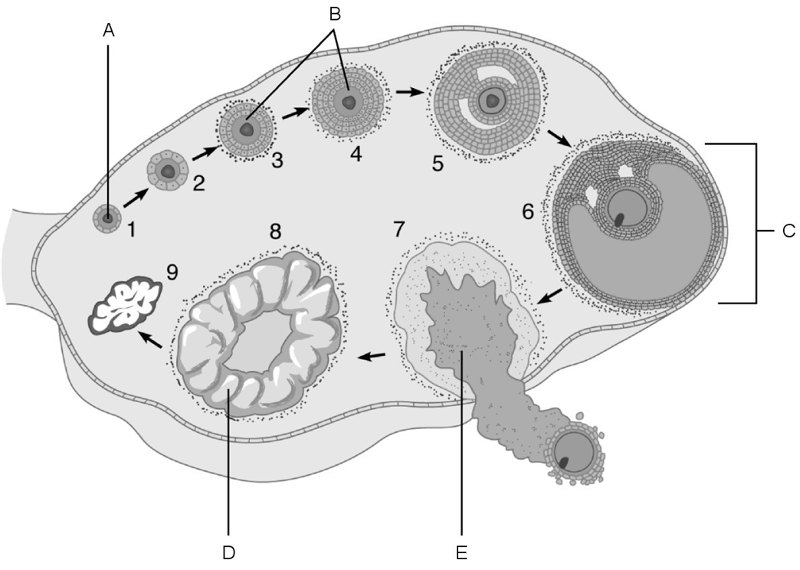

Afferent arteriole.

A

Cells that are most affected by ADH.

C

Cells that are the most active in reabsorbing the filtrate.

E

Medulla of the kidney.

E

Glomerulus.

C

Is composed of simple squamous epithelium.

A

Proximal convoluted tubule.

Site at which most of the tubular reabsorption occurs

Glomerulus.

Site of filtrate formation.

Peritubular capillaries.

Blood supply that directly receives substances from the tubular cells.

Collecting duct.

Site that drains distal convoluted tubule